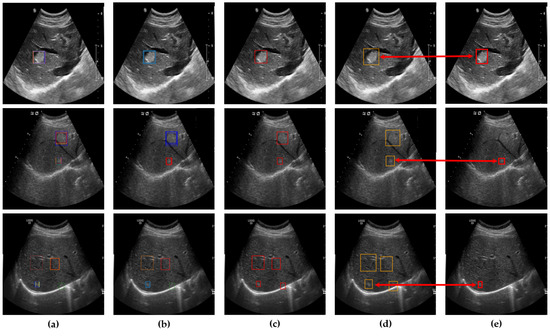

After clustering and outlier reduction, SM-WBF was applied to generate a single representative bounding box for each cluster. SM-WBF calculated weights for each bounding box by normalizing the mAP@0.5 values of the ten networks using the SoftMax function. These SoftMax weights were then used to combine the center coordinates and dimensions of the bounding boxes within each cluster through a weighted average approach. This method ensured that bounding boxes from higher-performing networks contributed more significantly to the result. Details of this process are illustrated in Figure 7.

Figure 5. Determination of bounding boxes using clustering, SM-WBF, and padding. (a) All bounding boxes detected by the ten networks. (b) Clustering of bounding boxes into four regions using DBSCAN. (c) Application of SM-WBF with SoftMax weights to the clustered regions. (d) Addition of padding to the bounding boxes in (c).

Figure 7. (a) An image with all bounding boxes detected by YOLOv8 overlaid, and the results of bounding box optimization through (b) clustering, (c) SM-WBF, and (d) padding. (e) Ground truth bounding box.